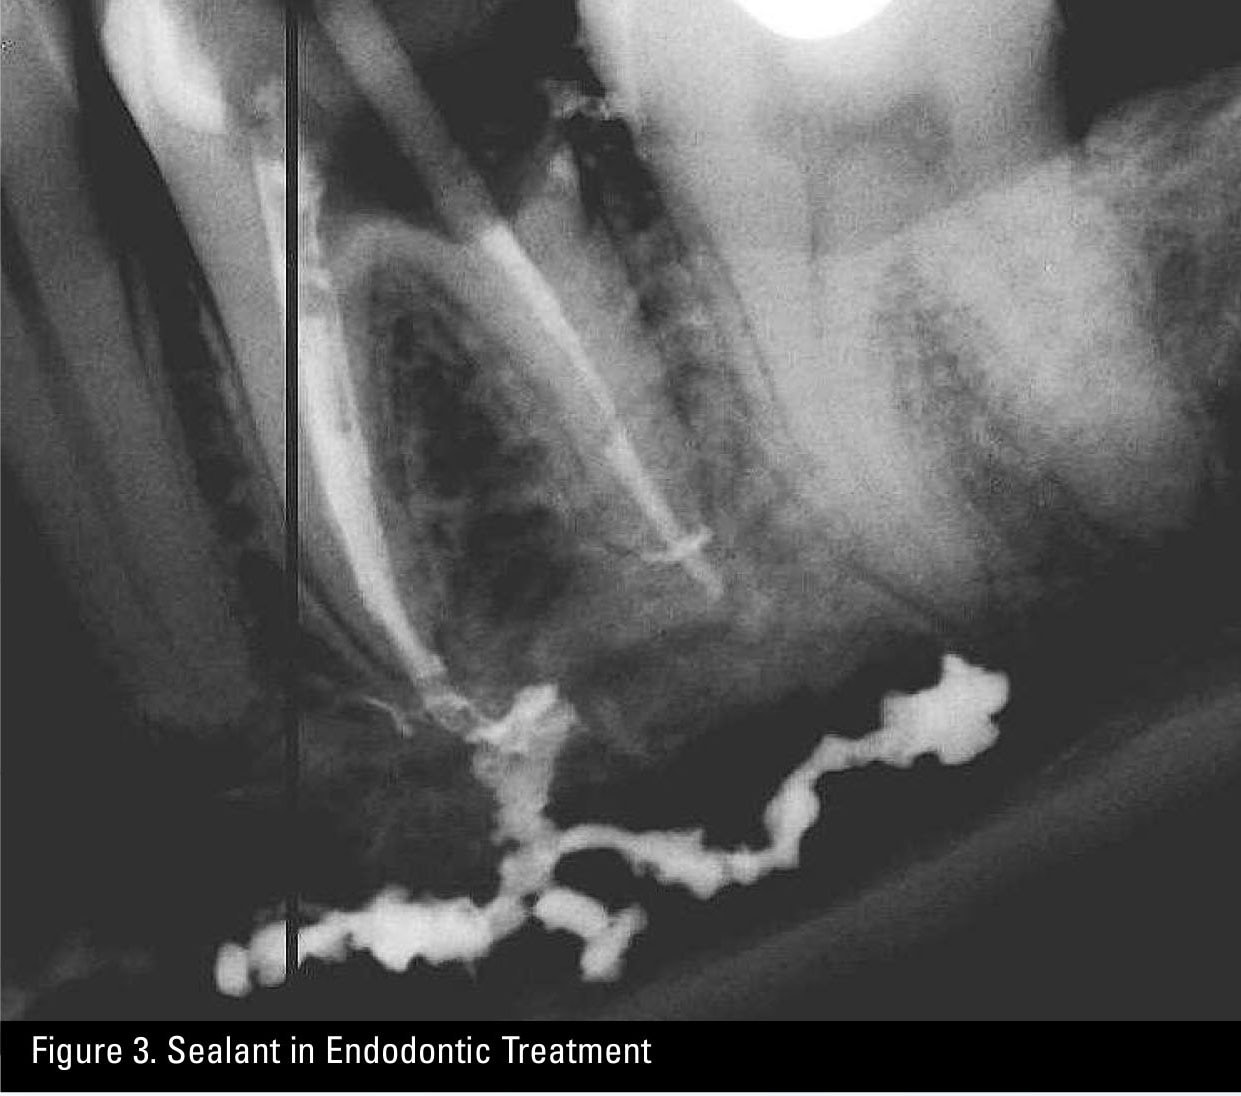

Sealant in Endodontic Treatment

A final observation is that the old adage that a picture is worth a thousand words is certainly true in dental radiology. A single radiograph may end up being the piece of information that actually helps plaintiff’s counsel to establish that there was indeed a deviation from the standard of care in treatment provided. By way of example, see Figure 2, a misplaced post, and Figure 3, over-exuberance in the use of sealant in endodontic therapy.